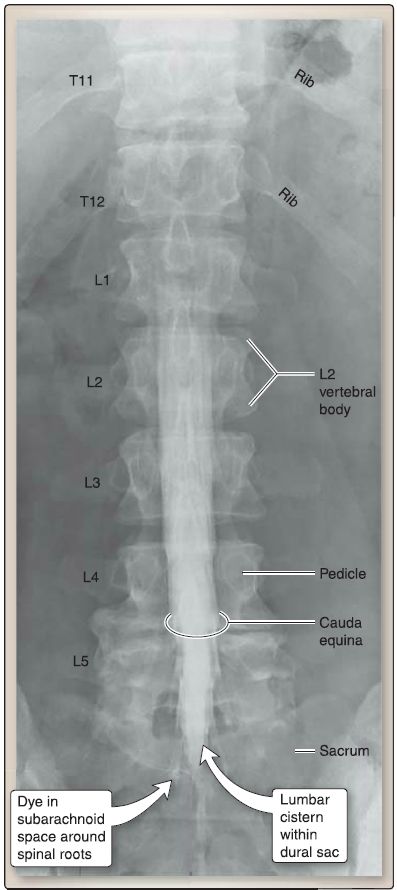

2. Arachnoid mater: Deep to the dura mater is the arachnoid mater, a delicate, web-like layer that creates a subarachnoid space filled with cerebrospinal fluid (CSF). CSF bathes and protects the spinal cord and nerve roots within the vertebral canal. The subarachnoid space also contains arterial and venous branches that nourish the spinal cord. Under normal conditions, the arachnoid and dura are closely associated, obliterating the subdural space between these two layers. However, bleeding can occur into this space, forming a subdural hematoma. A widened subarachnoid space exists below the level of the conus medullaris between vertebral levels L2-S2. This space, referred to as the lumbar cistern, lies within the dural sac and contains CSF and the cauda equina.

Figure 5 : Lumbosacral myelography.